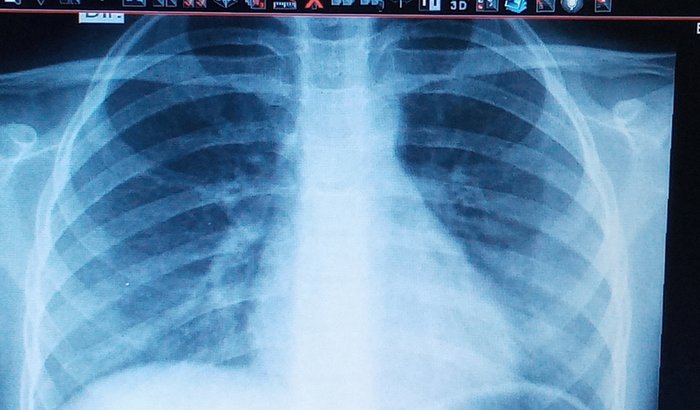

Saúde / Tratamentos

São Gonçalo / RJ